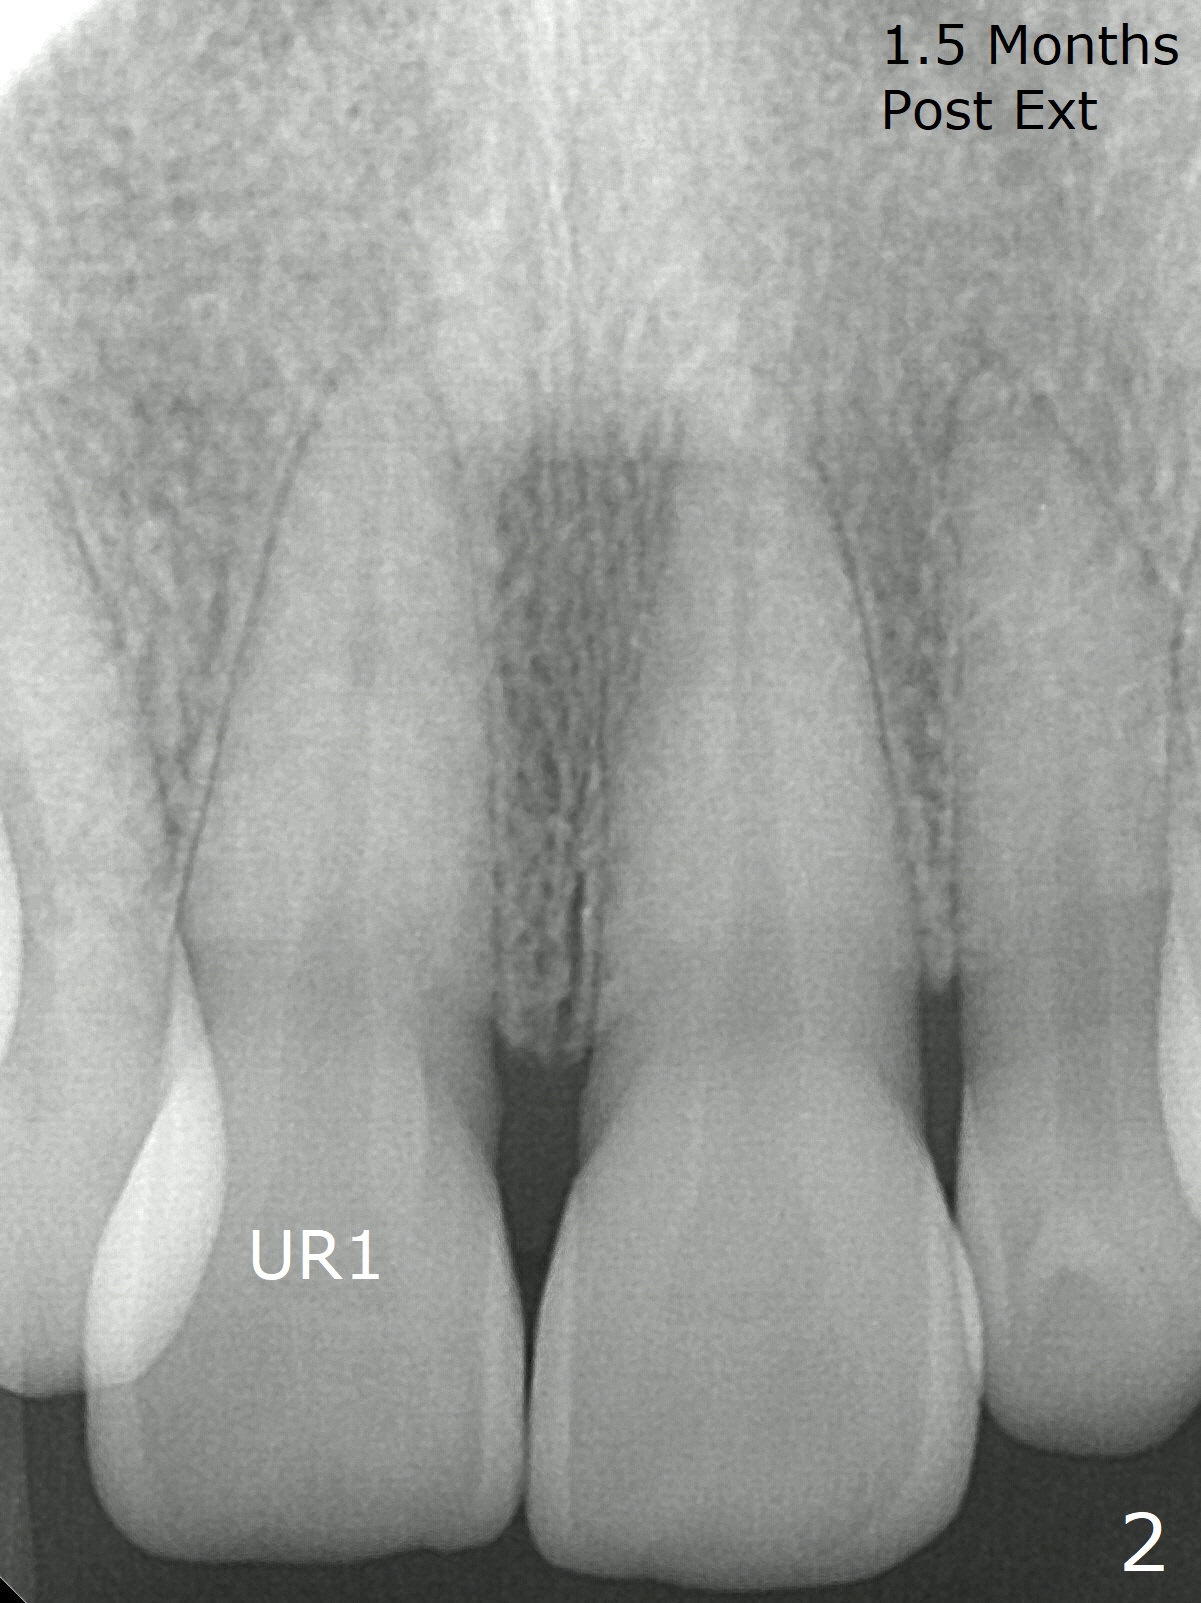

The 54-year-old woman returns for ortho-dontic treatment 1.5 months post extra-ction of UR2 (Fig.1,2). Brackets, bands and 14 niti wire are placed in the upper arch, whereas insufficient spaces are created for placement of the lower arch molar bands. Since there is no horizontal space issue, the cross bite canine is able to be corrected immediately when the vertical clearance is obtained (Fig.3,4). In fact composite is added to the 1st molars in a few days, since that in one of the 2nd molars dislodges. UR3 cross bite is nearly corrected < 2 months post banding (Fig.5), while brackets are placed in the lower arch (Fig.6 (coronavirus)). It appears that the lower arch will be too large when it is expanded for the upper one.